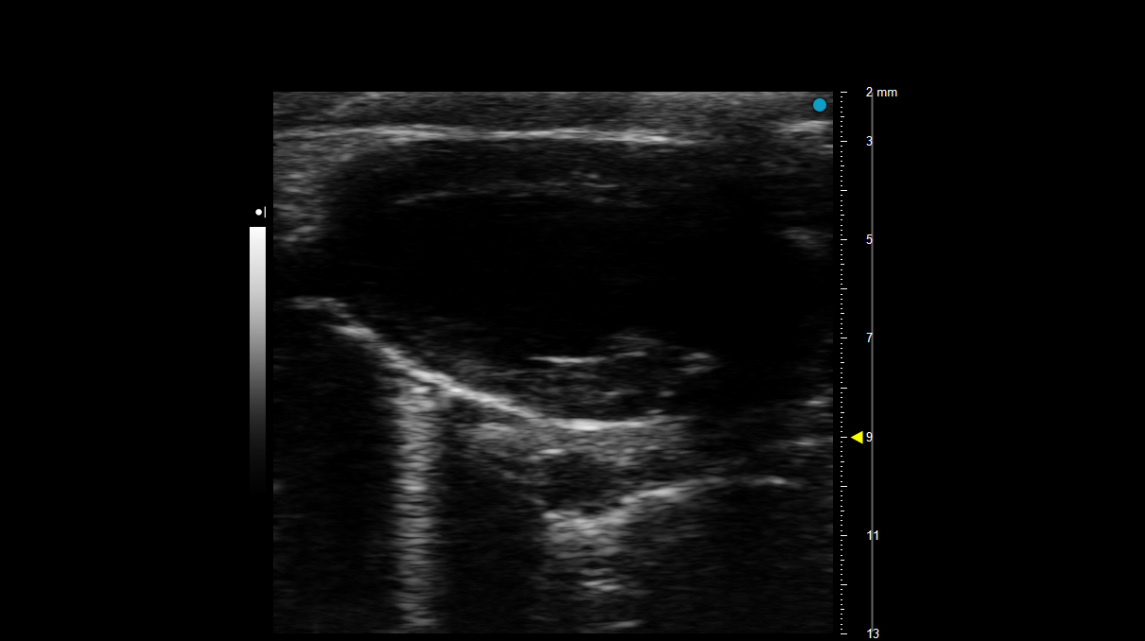

超声系统成像范围广,适合对软组织脏器、病变组织等进行观察和测量,但对肺成像困难。Visual sonic Vevo3100型超高分辨率小动物超声成像系统带有小鼠专用心电监测系统,在采集超声信号的同时记录小鼠心电信息,配合仪器的多普勒功能,不仅能够测量心室壁厚度等参数,还能够测量血流速度、射血分数、心室容积等反映心脏功能的参数。